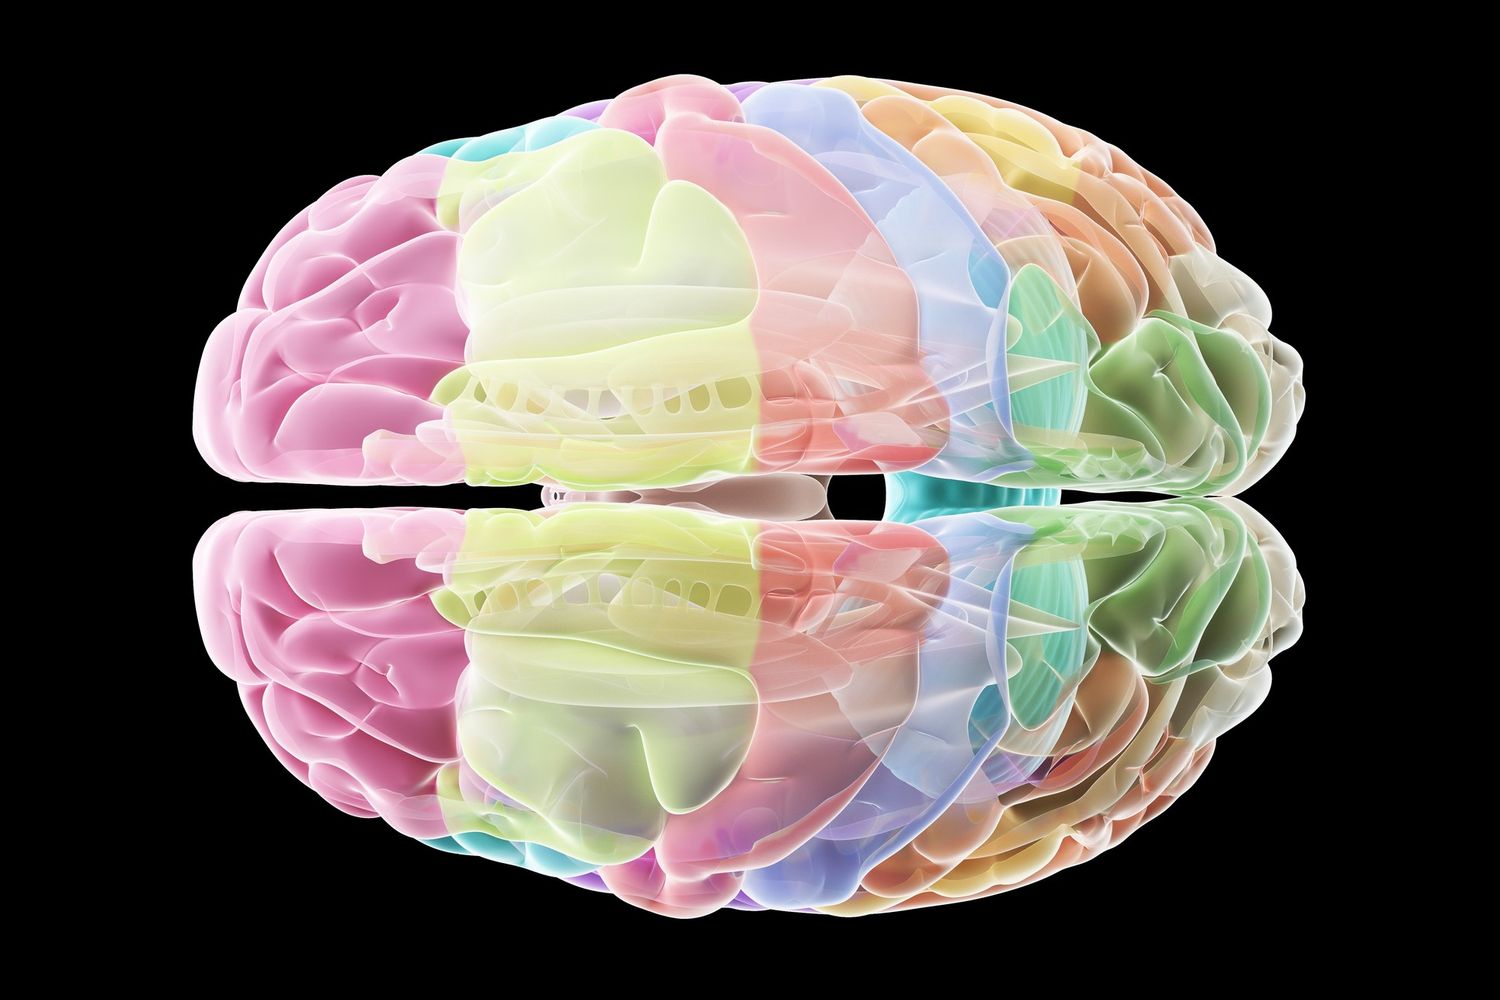

La corteccia cerebrale è la parte più esterna del nostro cervello ed è sede di funzioni cognitive complesse, quali il pensiero cosciente. Oltre ad essere la regione cerebrale più recente dal punto di vista evolutivo, è anche quella che, a causa della notevole espansione delle sue dimensioni, più contraddistingue come unico il cervello degli esseri umani quando paragonato ad altri animali.